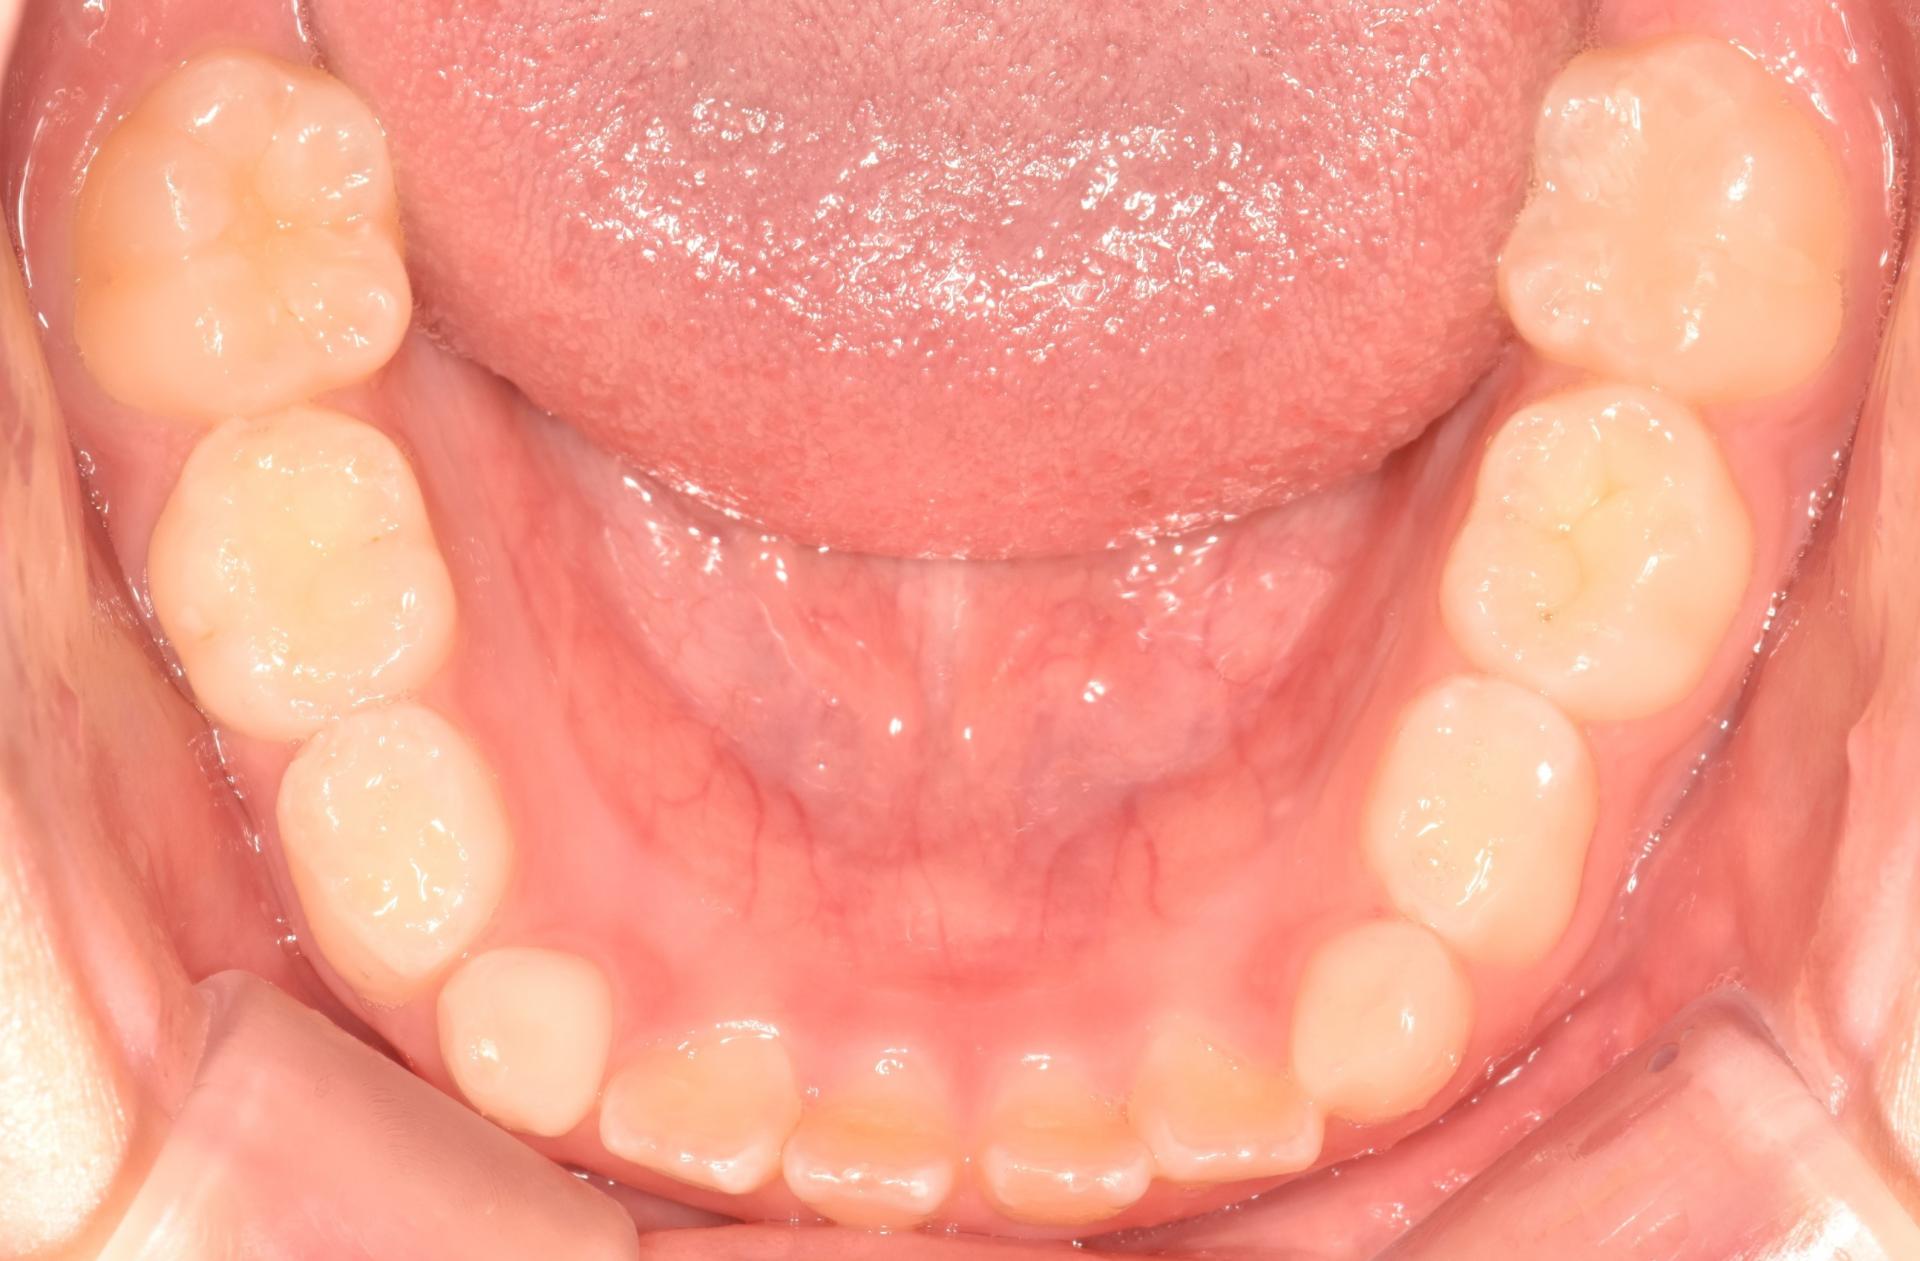

초진 사진입니다. 고르지 못한 앞니와 치아의 회전으로 인한 위아래 앞니의 부딪힘이 발생하고 있습니다. 또한 위아래 앞니의 뻐드러짐과 돌출이 보입니다.

아이는 투명교정으로 앞니의 배열과 확장을 통한 후속영구치의 맹출공간 확보를 하기로 하고 스캔을 진행하여 1년간 투명교정 장치를 성실하게 착용했습니다.

1년의 교정치료 기간 끝에 뻐드러진 치아도 안으로 예쁘게 넣었고 부딪히는 치아 없이 배열도 완료 되었습니다. 더불어 덧니되지 않도록 앞으로 나올 송곳니의 자리까지 마련했답니다.